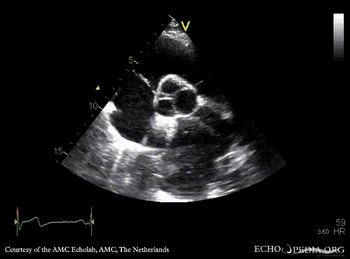

| PLAX: large cyst adjacent to left atrium, compression of LA | PSAX |